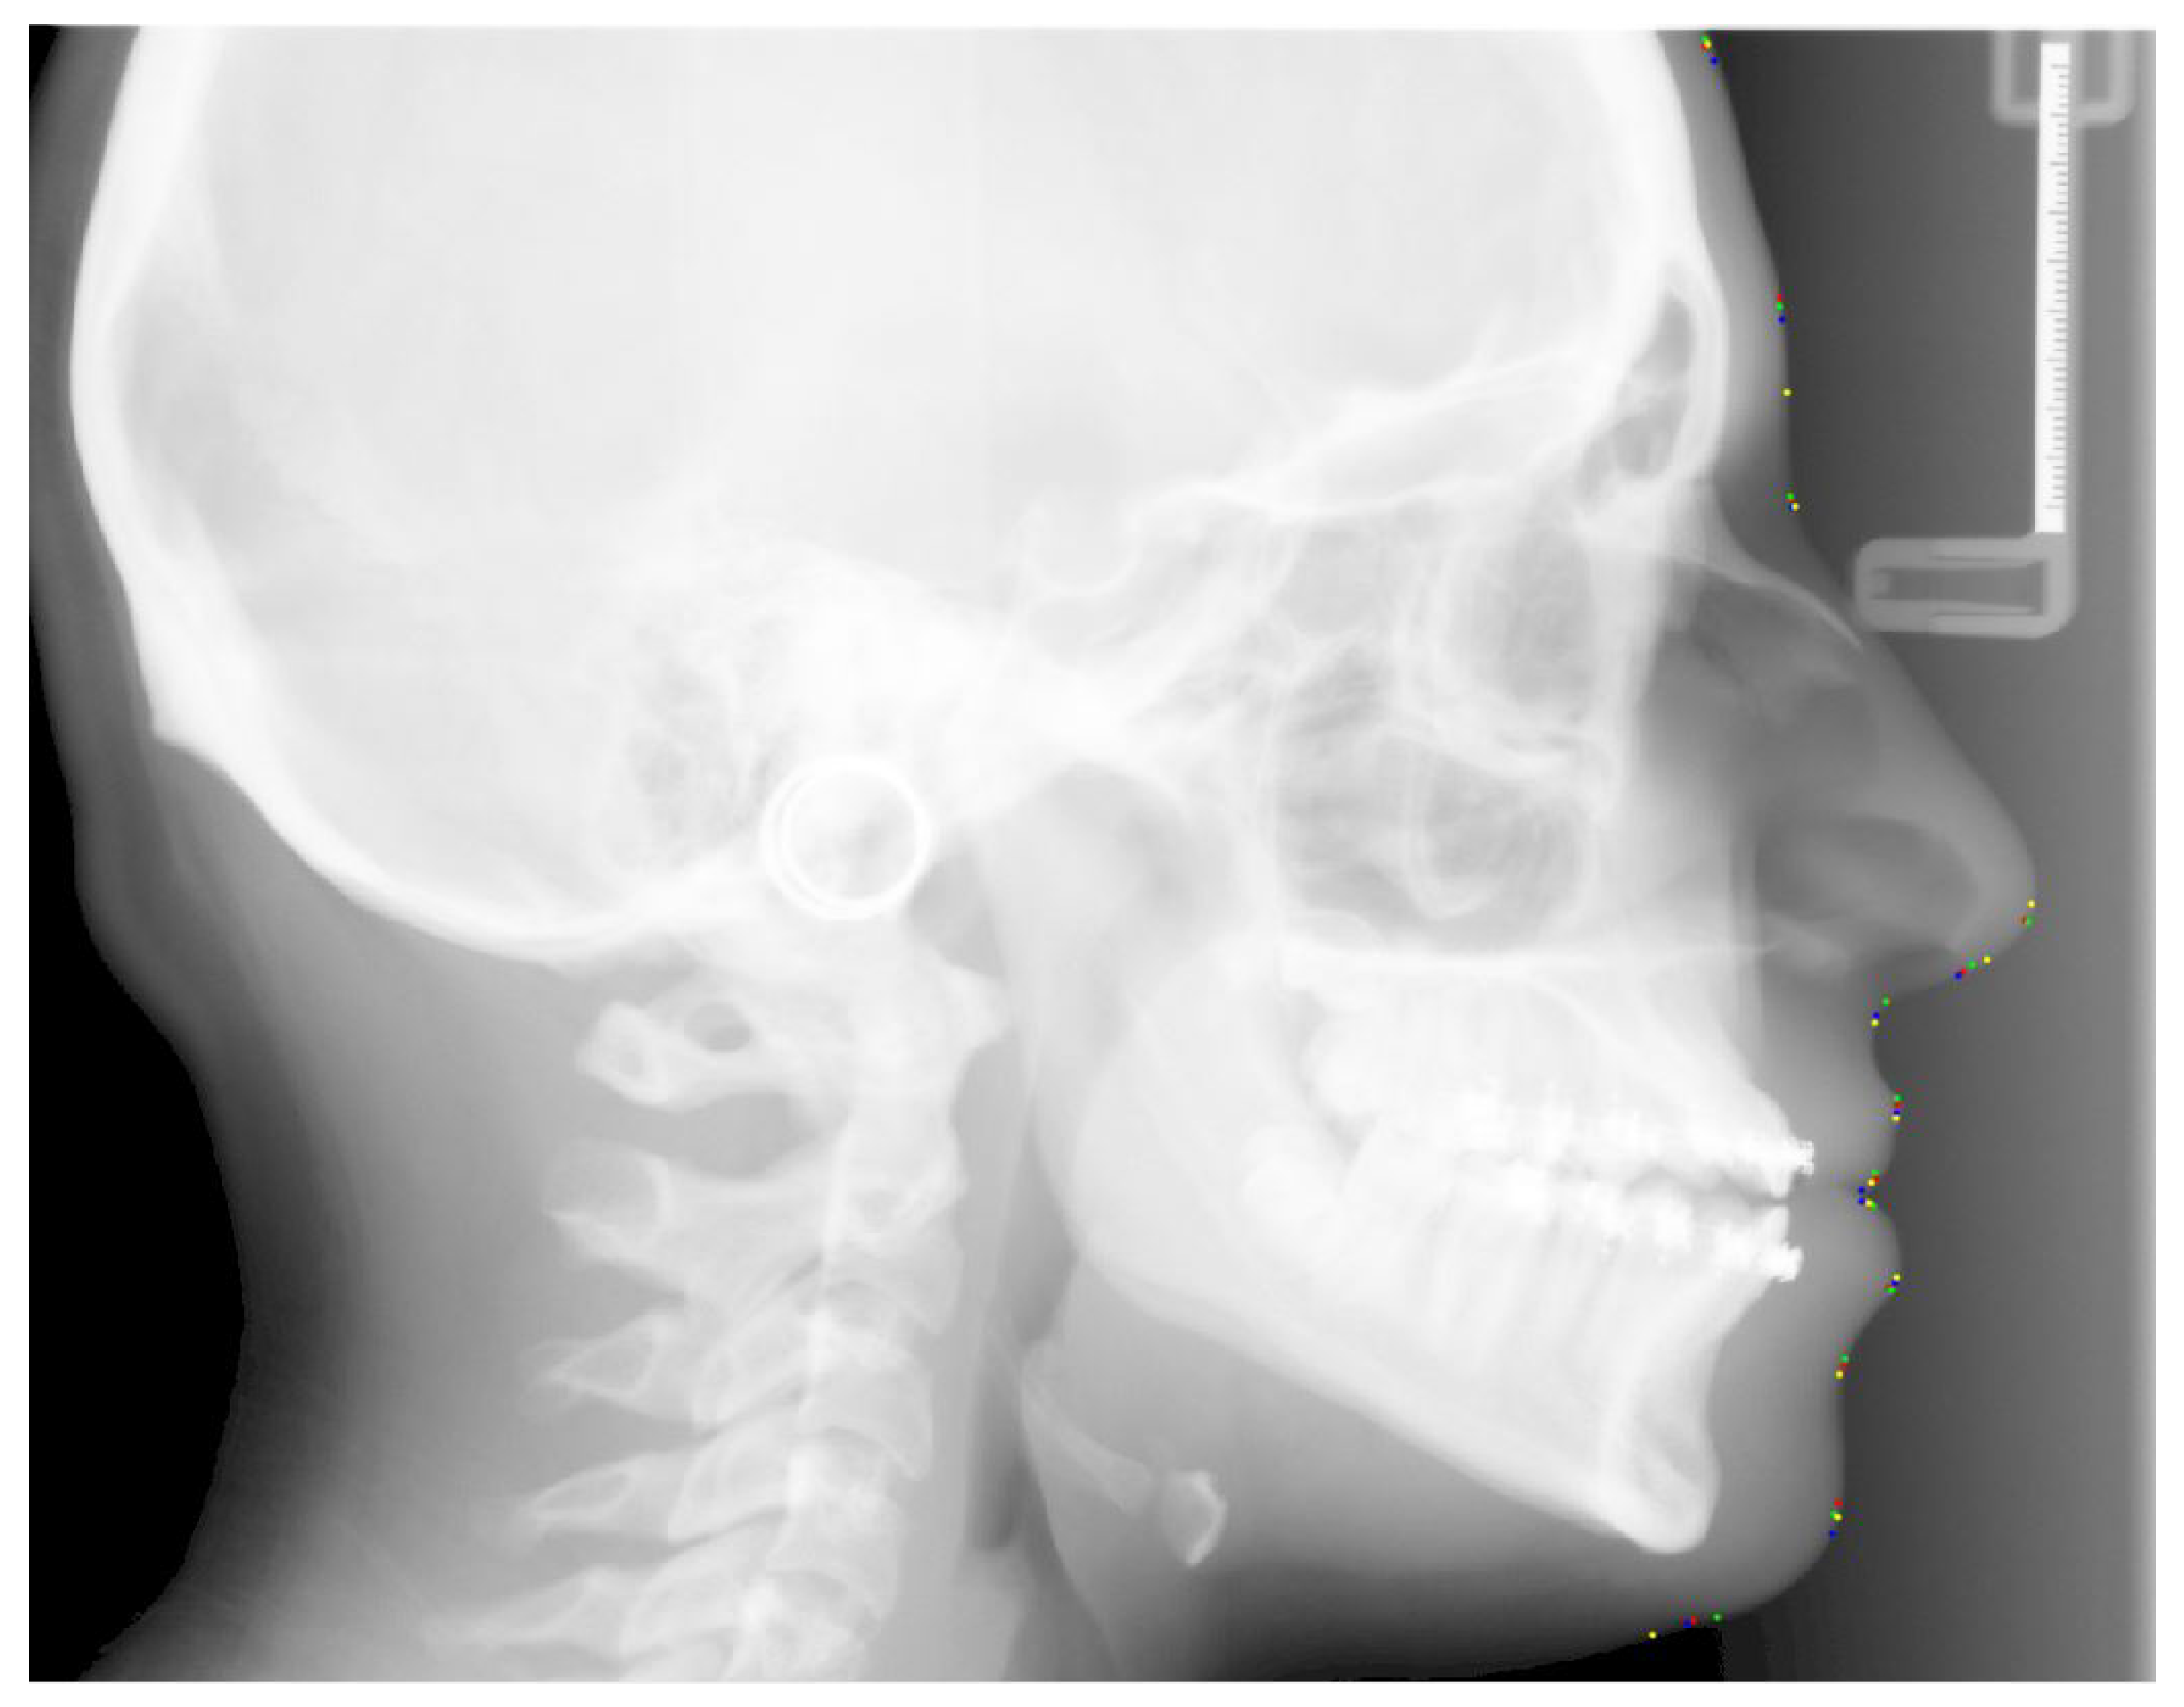

We can observe that the minimum variation is below 1 mm and the maximum variation for most landmarks is in the range of 1.5 mm to 5 mm except for the landmark G and Pg. It is due to the fact that they are the most difficult to identify. Similarly, the average variation for most landmarks is in the range of 1 mm to 2 mm except for the above-mentioned two landmarks. Figure 6 shows the variation in a sample X-ray image, and Figure 7 shows the variation of each landmark in the same X-ray image (red circle shows the variation area).

Figure 6. Graphical representation of variations of one sample image showing all the landmarks.